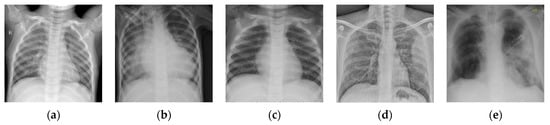

Figure 12.

Examples of rash images. (a,b) Non-Lyme disease; (c–e) Lyme disease.

To further validate the effectiveness of the proposed BSTriplet loss, some experiments have been conducted on a skin rash image dataset, which is used to distinguish the images containing Lyme disease from those with other disease [47]. The composition of the rash image dataset is listed in Table 7. Figure 12 shows some images in the rash image dataset. It can be seen that the images in this dataset are colorful optical images, which are much different from the above X-ray images. Besides this, the number of images in the rash image dataset is evidently less than that in the above datasets. To alleviate the over-fitting problem, we have augmented the training images by such methods as rotation by , and , horizontal/vertical flipping, and horizontal/vertical translation for five pixels so that the number of training images is enlarged by seven-fold. As for the test images, the augmentation has not been implemented. We have clustered the images into four categories, and built the input batches for the proposed CE+BST loss according to the steps in Section 2.3.